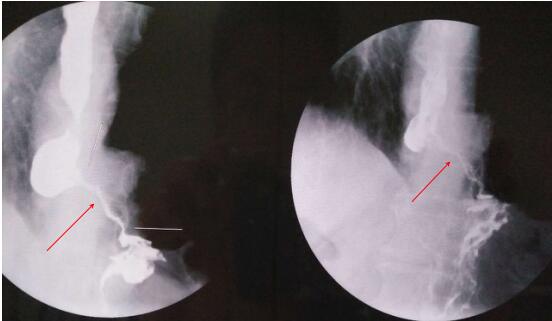

食道支架置入后(箭头所指为食道支架)

造影剂顺利通过支架进入胃内